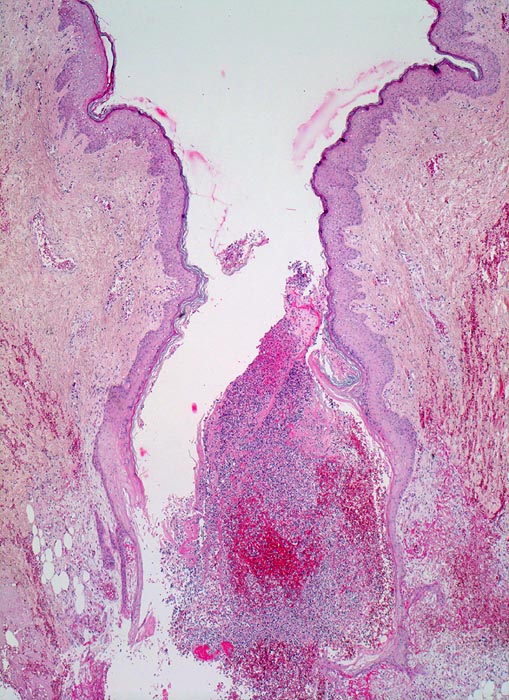

Morphologische Merkmale:

• Schlitzförmiger, bis in die Subkutis reichender Hautdefekt.

• Neugebildete Epidermis bedeckt im oberen intradermalen Anteil des Wundspaltes teilweise den Gewebsdefekt.

• Daran angrenzender Wundspalt im Bereich des subkutanen Fettgewebes mit Fibrinauflagerungen und ödematösem zellarmem Granulationsgewebe.

• An der Basis des Präparates Auseinanderklaffen des Wundspalts wegen grösserem Blutkoagel (verursacht Wundheilungsstörung).